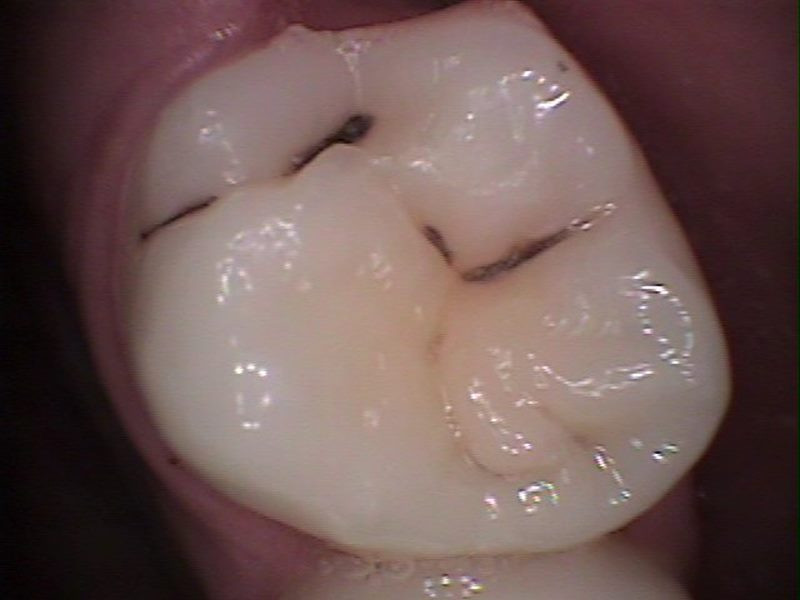

Antes

Molar superior con caries dental